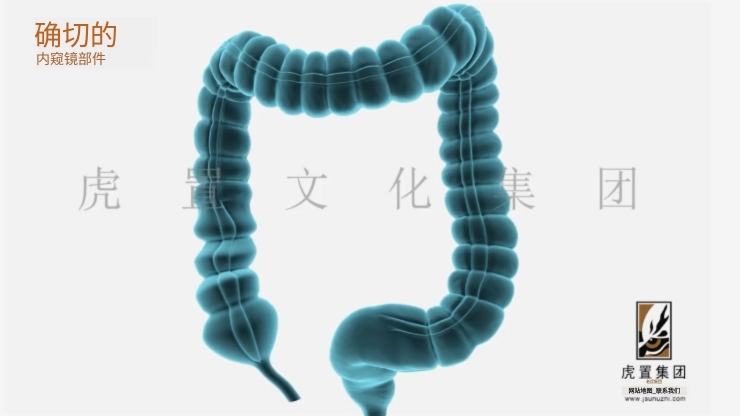

从项目规模来看,不同类型的3D动画制作所需时间差异显著。简单的产品展示动画,比如一个30秒的手机3D展示视频,通常需要2-4周完成。这类项目建模相对简单,动画效果要求不高,渲染时间也较短。中等复杂度的企业宣传片或建筑漫游动画,时长在1-3分钟的话,制作周期一般在4-8周。这类项目需要更精细的模型,更复杂的动画效果,以及更完善的后期处理。而大型影视级动画项目,如动画电影或电视剧集,则可能需要数月甚至数年的制作周期。其制作周期就长达8年,当然这包含了剧本创作等前期工作。

项目复杂度是影响制作周期的另一个关键因素。角色动画的制作周期通常比产品动画长很多,因为需要设计角色模型、骨骼绑定、表情系统等。一个30秒的角色动画可能需要6-8周,而同样时长的产品动画可能只需3-4周。特效的复杂程度也会显著影响制作时间,流体模拟、毛发渲染等高级特效都需要额外的时间投入。此外,场景的复杂程度、是否需要物理模拟等因素都会对制作周期产生重要影响。

制作流程的每个环节都会占用一定时间。前期策划阶段包括创意构思、脚本撰写、分镜设计等,通常需要1-2周。这个阶段看似不直接产出画面,但好的前期规划能大幅提升后续工作效率。3D建模阶段根据复杂度不同需要1-3周,高精度模型可能需要更长时间。材质贴图需要1周左右,灯光设置也需要几天到一周不等。动画制作阶段,简单的产品动画可能只需几天,而复杂的角色动画可能需要数周。渲染环节往往是最耗时的,一帧高质量的渲染可能需要数小时,一个1分钟的项目可能需要数千小时的渲染时间。后期合成包括调色、特效合成等,通常需要1-2周。

虎置集团一直专注于产品动画、卡通动画、影视广告、3D效果图等综合设计服务。拥有北、上、广、深四大数字科技创意中心,国内先进的研发团队和用户体验研究实验室,新锐设计师及软硬件工程师超过100人。20年来,雄厚的技术实力助力虎置打造数字产品项目超过100个,累积设计数字项目500个,行业标杆性项目愈十个。